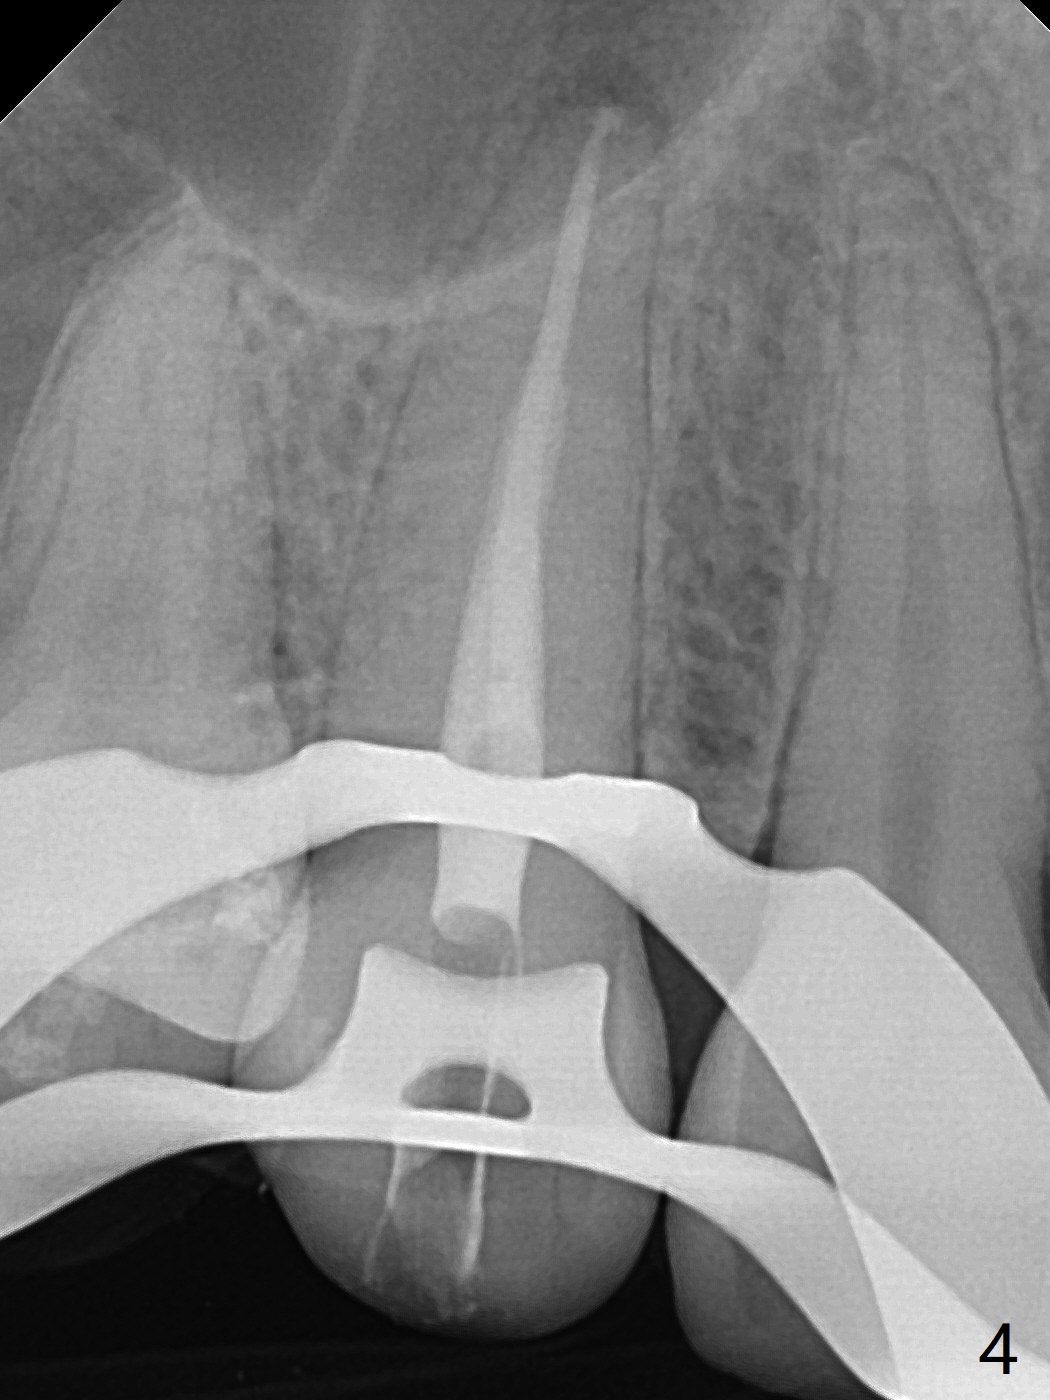

A 36-year-old woman (after #3 immediate implant and #31 socket preservation) wants to take care of the discolored canine 20 years post orthodontic treatment with extraction (Fig.1-3). RCT (Fig.4) appears to whiten the tooth (Fig.5 (A4)). The darkness appears to rebound 1 month post RCT, after removal of Gutta Percha for take home internal and external bleaching (Fig.6). The patient returns for composite after 3-week whitening (Fig.7,8). The shades of composite are bleach (flowable, C1) and B1 (packable, C2, Fig.9). The shade of the RCT tooth is compatible with that of the neighboring teeth 4 months post composite (Fig.10) when the implant at #3 has a new abutment.